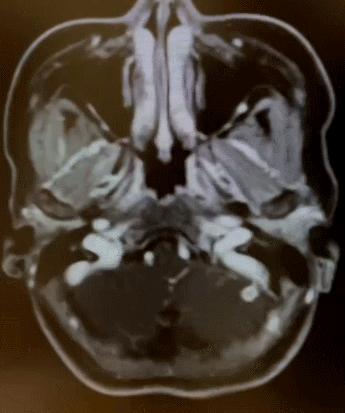

张思医生介绍到,通过小王的头颅增强MRI可以看到,她的脑中有许许多多的“小白点”↓

▲头颅增强MRI显示颅内多发“白色”强化病灶

张思医生解释道,这样的颅内多发强化病灶,是脑寄生虫感染的常见影像学表现。再加上小王平时也有爱吃“醉虾、未充分煮熟的坨坨肉”等美食的习惯。

因此,高度怀疑小王患的是一种叫“脑囊虫病”的寄生虫感染。